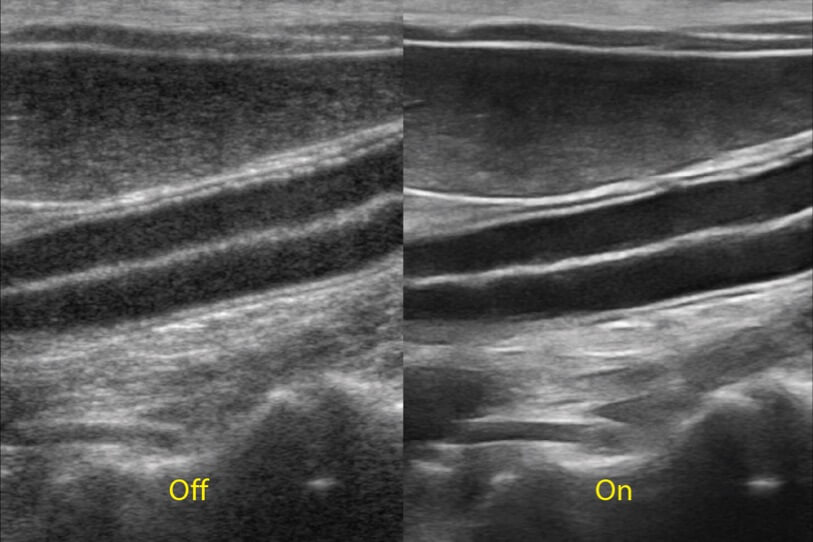

ProPet 70 進(jìn)一步提升了微米成像算法,更加注重對(duì)基礎(chǔ)原始圖像的還原和保留,在有效減少斑點(diǎn)噪聲、增強(qiáng)組織邊界顯示的同時(shí),避免過(guò)度優(yōu)化丟失真實(shí)的解剖信息。

增強(qiáng)穿刺針在動(dòng)物解剖結(jié)構(gòu)中的位置,提高穿刺介入的安全性和準(zhǔn)確性。